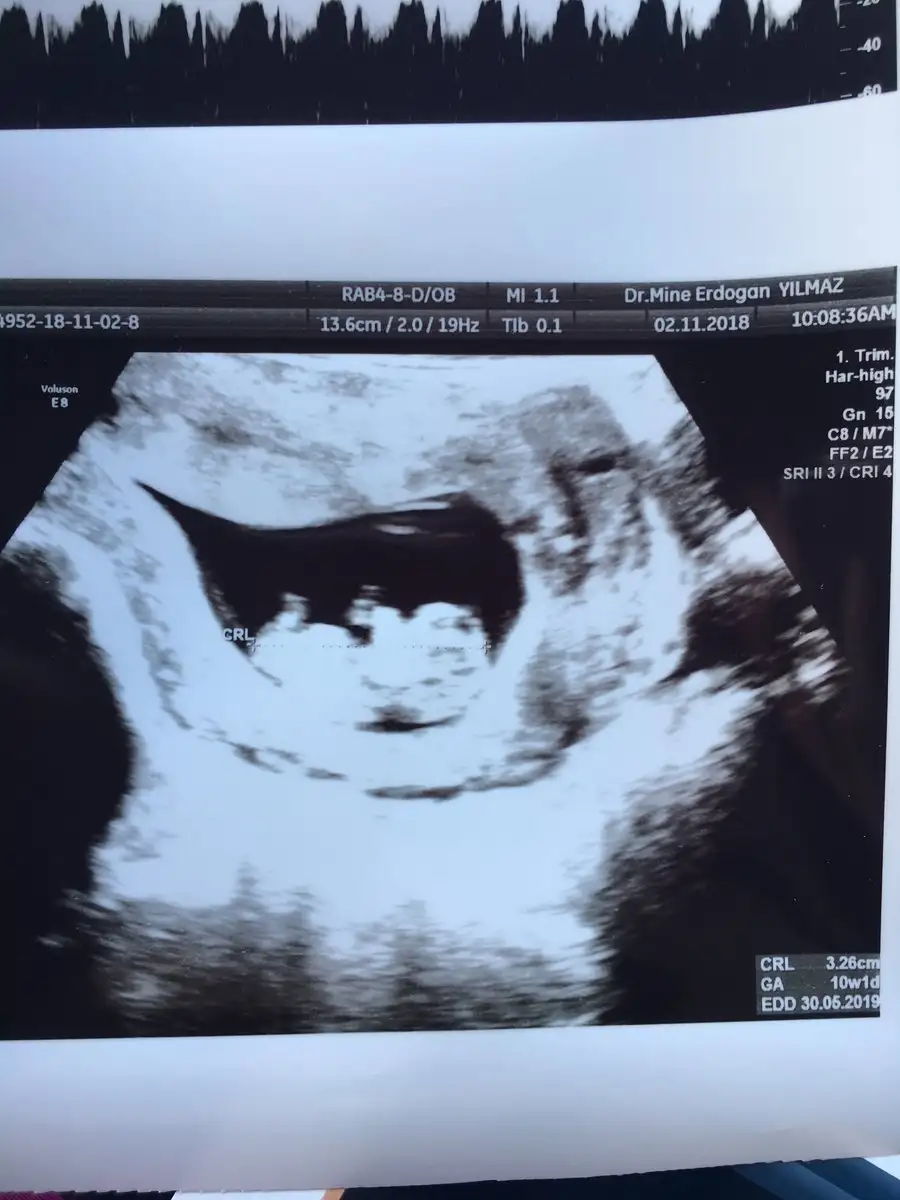

Evet canımm sen naptın senin ne zamandı randevun? Bu arada benim tembel hiç ama hiç hareket etmiyor :) doktor neler yaptı hareket etsin diye ama cıks :) kalbi maşallh çok iyi atıyo ama uyuyodu sanırınYaaaaakocaman olmuş annesi maşallah

nasıl büyüymüş ay maşallahKızlaaaaaarrrr

Bende fotoğrafta kız bebeğine benzettim boyle yuvarlak yuzlu kız çocugu gibi geldi ama hayırlı ve sağlıklı olsun inşallahAyy hadi inşallah önce sağlıklı sonra kızdır inşallah:))

Maşallah yaKızlaaaaaarrrr